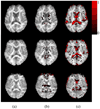

This article presents two related advancements to the diffusional kurtosis imaging estimation framework to increase its robustness to noise, motion, and imaging artifacts. The first advancement substantially improves the estimation of diffusion and kurtosis tensors parameterizing the diffusional kurtosis imaging model. Rather than utilizing conventional unconstrained least squares methods, the tensor estimation problem is formulated as linearly constrained linear least squares, where the constraints ensure physically and/or biologically plausible tensor estimates. The exact solution to the constrained problem is found via convex quadratic programming methods or, alternatively, an approximate solution is determined through a fast heuristic algorithm. The computationally more demanding quadratic programming-based method is more flexible, allowing for an arbitrary number of diffusion weightings and different gradient sets for each diffusion weighting. The heuristic algorithm is suitable for real-time settings such as on clinical scanners, where run time is crucial. The advantage offered by the proposed constrained algorithms is demonstrated using in vivo human brain images. The proposed constrained methods allow for shorter scan times and/or higher spatial resolution for a given fidelity of the diffusional kurtosis imaging parametric maps. The second advancement increases the efficiency and accuracy of the estimation of mean and radial kurtoses by applying exact closed-form formulae.